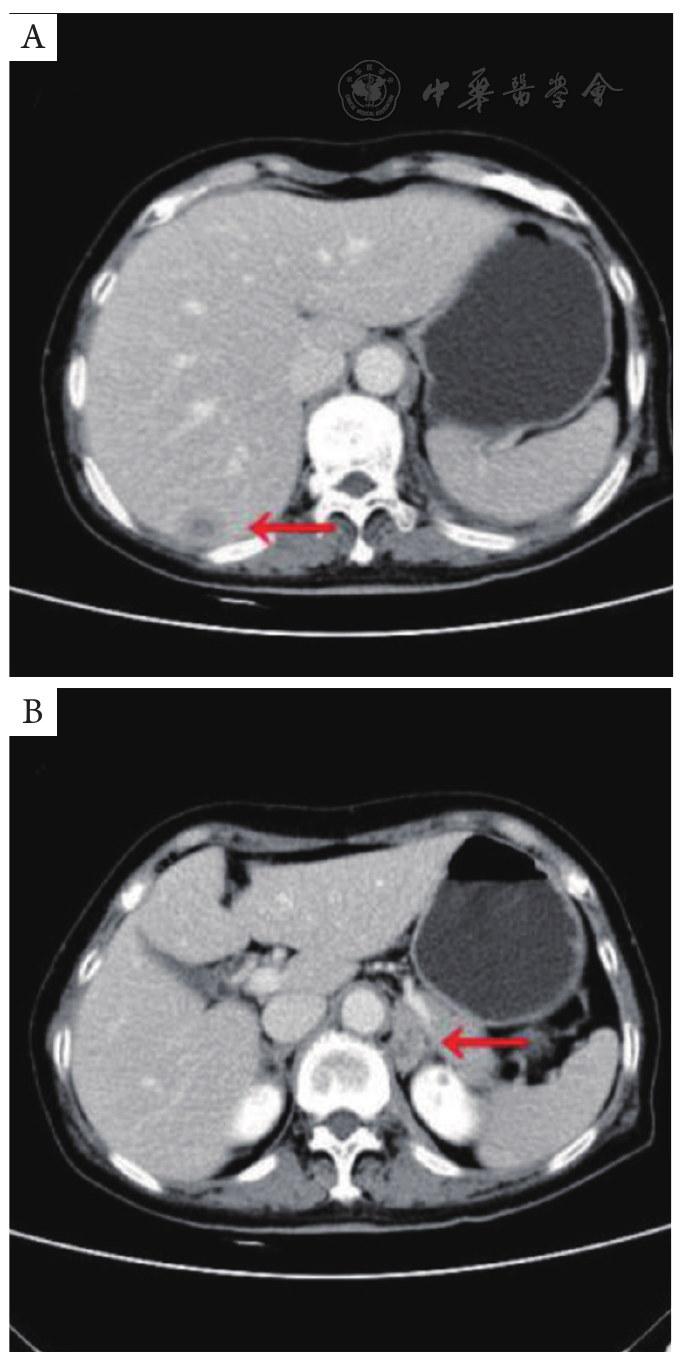

图4 全腹部增强CT(2022年10月20日)。A:肝右叶转移瘤(红色箭头),增强扫描呈典型"牛眼征";B:左侧肾上腺转移瘤(红色箭头)。CT:计算机断层扫描